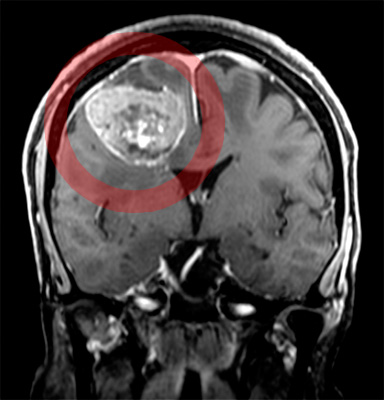

頭部CTあるいはMRI検査で、腫瘍あるいは周囲の脳の浮腫みといった異常所見を認めて、発見されることがほとんどです。

転移性脳腫瘍が疑われると、造影剤を用いたMRI検査や核医学検査等の検査を行います。また転移性腫瘍が発覚することで、原発巣(原発癌)を調べるきっかけになることも稀ながらあります。